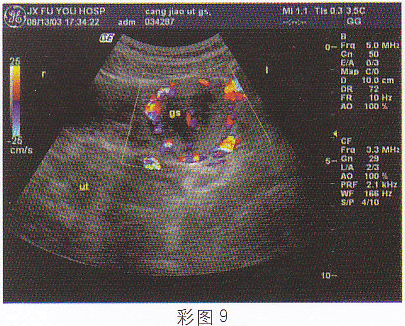

4.女,28歲,停經46天,陰道不規則出血5天,血HCG68μg/ml,結合超聲圖像,最可能的診斷為(彩圖9)

正確答案:D 解題思路:附件區見囊實混合性光團,邊界尚清晰,子宮腔內有分離患者有停經,不規則陰道出血,且血HCG增高。